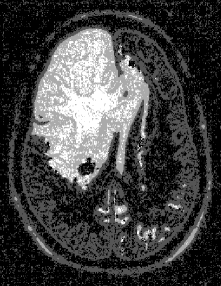

Figure 6a555From the Iowa Neuroradiology Library (http://www.uiowa.edu/c064s01/index.html). Used with permission. shows an MRI image of a brain with a tumor in the upper left quadrant. The segmented image using the direct Potts segmentation method with and is shown in Fig. 6b. After filtering, we obtain the the image in Fig. 6c. Here, the white regions may be interpreted as possible tumorous tissue, light gray corresponds to matter at the periphery of the tumor, dark gray represents cerebrum, and black is other brain matter. Automated screening for tumors may be performed by finding white regions of significant size. Although, the four-level histogram method (Fig. 6d) also identifies a similar tumor region, the cerebrum is not distinguished from other brain matter. The affect of the chosen value for is demonstrated in Fig. 7. Larger values of result in more of the image being categorized as textured (represented as light and dark gray). Finally, acoustic seafloor images may be analyzed in real-time with the direct Potts segmentation method as demonstrated in Fig. 8. Here sand ripples are identified (in green) as a grainy texture and is separated from the remainder of the image. Rapid seafloor characterization enables effective mine hunting/avoidance operations bentrem06 ; bentrem02 ; bentrem08 , by indicating where seafloor mines are likely to be buried (mud), partially buried (sand), or unburied (rock).